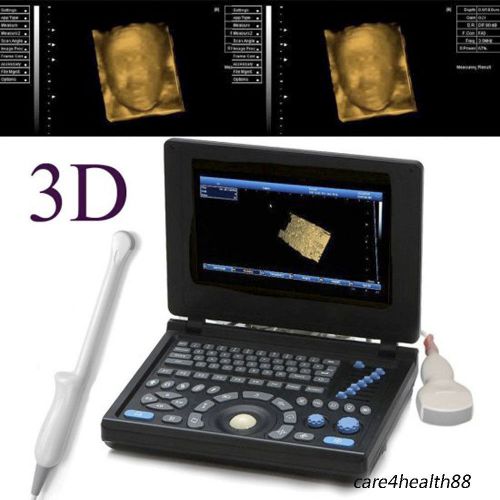

Model | RUS-9000E2 |

3D PC Full-digital Ultrasound scanner machine 3.5MHz Convex + Linear+ Tvaginal

3D PC Full-digital Ultrasound scanner machine 3.5MHz Convex +mirco-Convex probe

3D Full Digital Laptop Ultrasound Scanner (PC) With Convex probe & Transvaginal